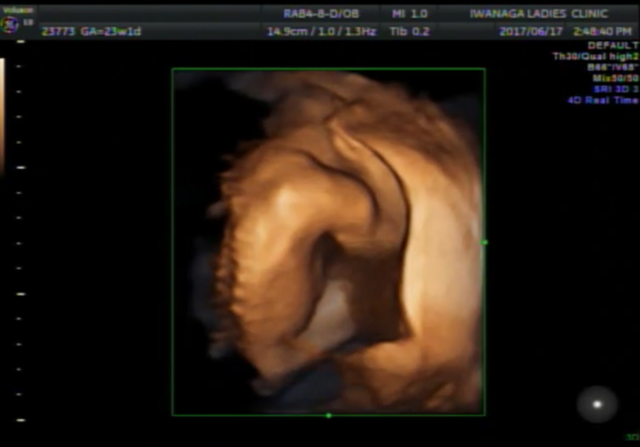

23週0日(23w0d・男の子)|☆あまちゃん☆ さん(27歳)

エコー写真撮影時のエピソード:

2回目の3Dエコー。しっかり横顔を見せてくれました‼︎ 何枚かあった中でファイティングポーズの様な写真。

3Dエコーで赤ちゃんの顔が見れたことによって、成長しているんだなーとうれしく思った記憶があります。生まれてからも手足をバタバタ、戦ってるようです!